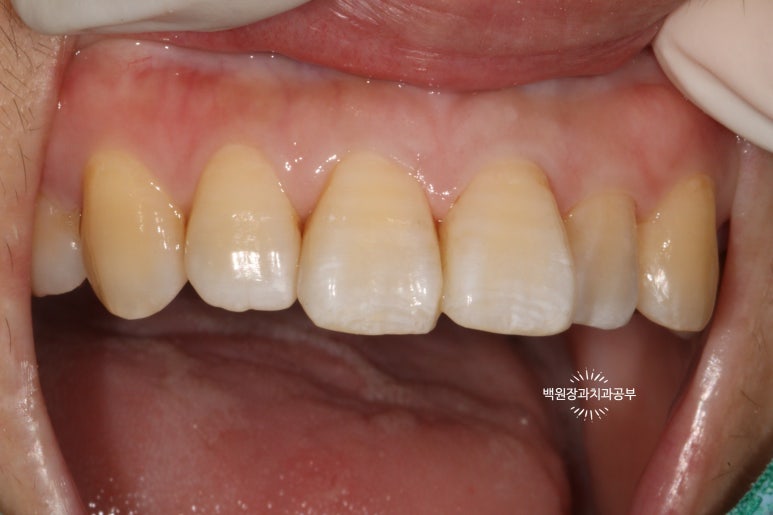

치과의사만 볼 수 있는 치아 뒷면 !!

사실 자기 앞니의 뒷면을 본 다는 것이 쉽지는 않습니다만..

치과의사는 뒷면을 볼 수 있습니다 !!!

딱 보아도 충치가 있는 걸 아실 수 있죠?

까맣게 보이는 부위들이 치아 옆면의 충치들입니다.

충치가 클 경우 지르코니아 크라운이나 PFM 크라운 치료를 권해드리지만,

이번에는 3M 레진을 이용하여 레진치료로 하기로 결정했어요!!